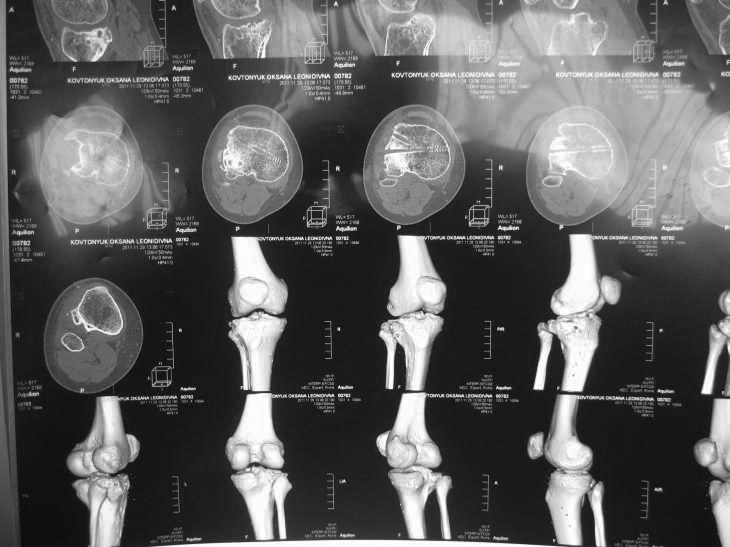

Надо на КТ посмотреть для планирования.

Мне кажется, нужно понять характер полученного перелома тибиального плато, степень и характер смещения отломков, есть ли дефект поверхности тибиального плато. На все это ответит КТ исследование! Тогда Вы тут остеотомией ничего не получите. Дообследуйте пациентку.

Жалобы на деформацию и нарушение функции правого коленного сустава .Внешний вид –вальгусная деформация на уровне коленного сустава .Коленный сустав стабильный, надколенник при сгибании в правильном положении.

Игорь Вы правы. мне кажется,надо менять наклон наружного плато,чтобы слегка "утопить" межмыщелковое возвышение.Для этого нужна остеотомия наружного мыщелка(косая,но по направлению к межмыщелковому возвышению.Коррекция только угловая с костной пластикой открывшегося угла. Ревизия сустава обязательна.